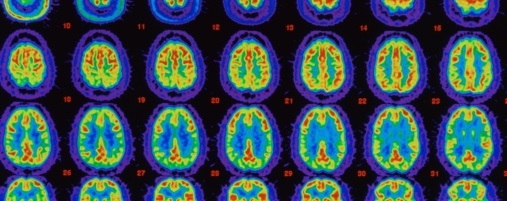

Tomografia de encéfalo com Alzheimer. A cor vermelha mostra o fluxo sanguíneo máximo, o verde-amarelo indica menor fluxo de sangue, enquanto áreas em roxo, azul e verde escuro indicam nenhum fluxo. Jonathan Selig via Getty Images.

8. Alzheimer pode ser transmissível

É possível transmitir a doença de Alzheimer de uma pessoa para outra, de acordo com um estudo publicado ontem na revista Nature feito por cientistas da University College de Londres. Você não pode pegar a doença de Alzheimer por cuidar de alguém com a doença de Alzheimer. Mas, a transmissão pode ocorrer em situações inusitadas envolvendo contato direto com o tecido cerebral como em neurocirurgias através de material cirúrgico contaminado. A contaminação faz com que haja deposição de proteína beta-amilóide que causa Alzheimer no cérebro da outra pessoa afetando ao longo dos anos a memória e o raciocínio.